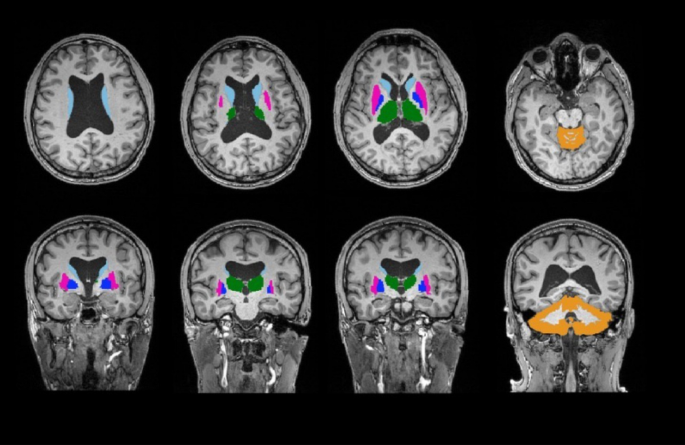

For non-cortical ROI, we examined the volumetric differences in the bilateral putamen, caudate, globus pallidus, thalamus, and cerebellar gray matter (Fig. 1). Factors such as estimated intracranial volume, sex, and age were incorporated as covariates in our analytical model. We employed permutation testing for statistical inference, with a total of 10,000 permutations conducted. The significance level was established at α = 0.05, adjusted for false discovery rate (FDR) correction.

FreeSurfer Subcortical Segmentation Regions of Interest (ROI) of one subject. ROI include bilateral Cerebellum cortex (orange), Thalamus (green), Caudate (light blue), Putamen (pink), and Pallidum (purple). The top-left image presents a sagittal view, the top-right displays a coronal view, the bottom-left shows an axial view.